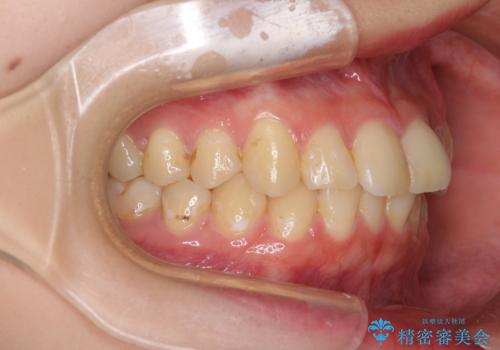

- 上下前歯のデコボコを気にして来院された患者様です。

以前矯正をした後戻りということで、歯列不正はそれほど大きくなかったため、インビザライン・ライトを用いて矯正治療を行うこととしました。

前歯のデコボコが残っており、シミュレーション通りに動いていない部分がありましたが、再矯正であることやご本人の満足いくところまでデコボコが改善されたとのことで、治療を終了することとしました。